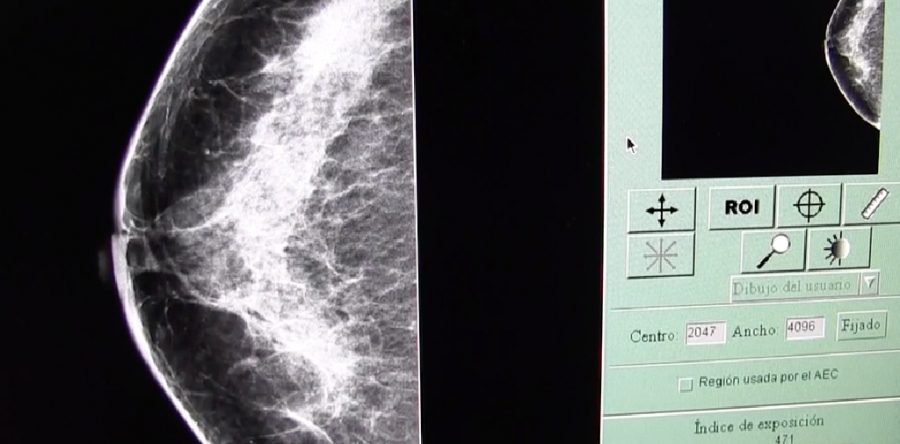

De los casos reportados en 2018, el 55 por ciento se presenta en mujeres mayores de 40 años, seguido de las de 35, 38 y 26 años; por lo anterior, se recomiendan los estudios de mastografía, cuya importancia en la detección temprana ha permitido reducir en un 40 por ciento el número de defunciones.

Asimismo, a través de las unidades móviles de detección se han realizado, de enero a la fecha, 25 mil mastografías, rebasando la meta de 2017.